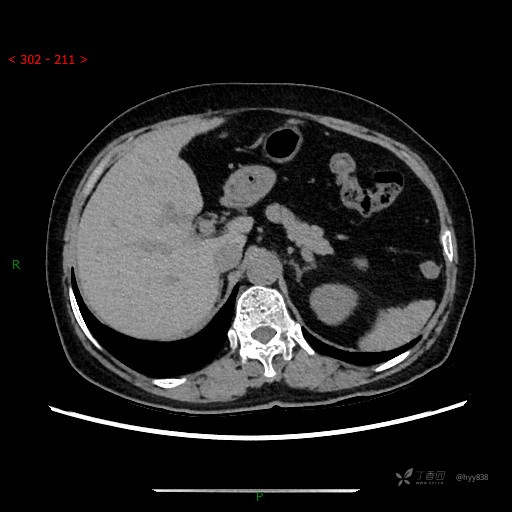

静脉期